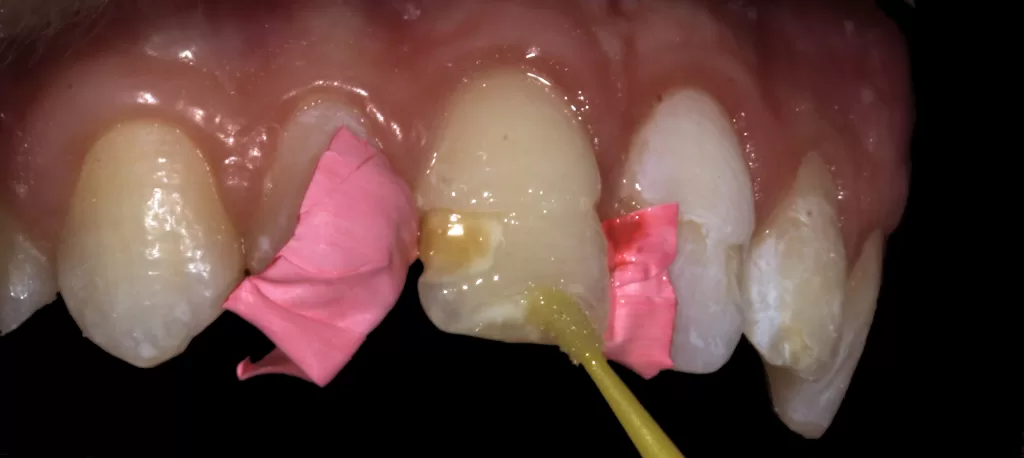

- Enamel and dentine sandblasted with Aquacare Twin Aluminium Oxide 29 micron, rinsed and dried (Fig 3).

- Phosphoric acid etch for 15 seconds, washed and dried to frosted appearance (Figs 4a & 4b).

- Scotchbond Universal Adhesive (3M, St. Paul, Minneapolis, United States), rubbed 20 seconds, gentle air dry to dissolve the solvent, light cured 10 seconds (Fig 5).